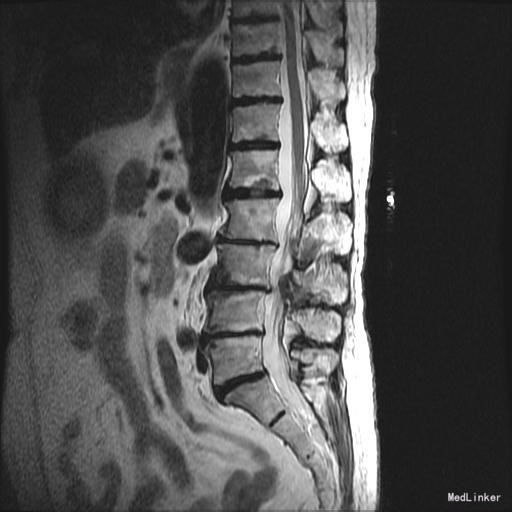

查体:脊柱无明显侧弯,腰背部无压痛,双下肢麻木酸痛,可牵连至脚跟。肌力肌张力可。腰部活动可,前屈后伸时感酸痛,无力。左侧直腿抬高试验阳性。 辅助检查:X线平片:腰椎侧弯前屈,L3椎体轻度滑脱,各椎间隙狭窄,腰椎退行性改变。 MRI:L4-5,L5-S1椎间盘膨出,L2-3,L3-4,L5-S1椎间隙狭窄,S2-3水平骶管内蛛网膜囊肿,腰椎序列不稳定,生理曲度局部后凸。

诊断:1 脊柱侧弯 伴不稳 2椎管狭窄 治疗: 前期微创腰椎侧路融合手术+后期 微创后路经皮内固定